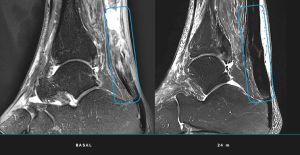

- Regeneración total: Las resonancias magnéticas confirmaron que todos los pacientes alcanzaron la regeneración completa del tendón al término del seguimiento de 24 meses.